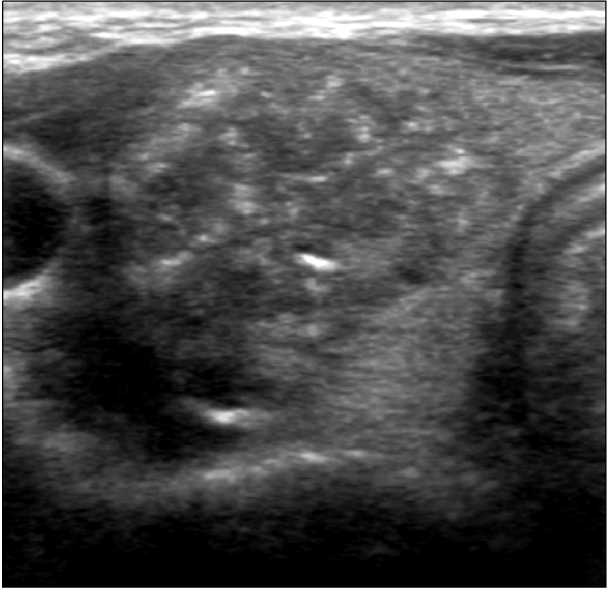

결절 내부의 미세석회화(microcalcification): 결절 안에 작은 석회질 덩어리가 꽉 차 있는 것을 말합니다.

저에코(hypoechogenic n odule) : 초음파에서 다른 조직에 비해 더 어두워 보이는 병변을 말합니다.